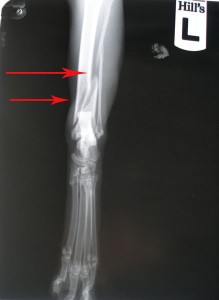

Po operaci obou kostí

kontrolní rentgen měsíc po operaci: 467,-Kč

Teď nás čeká další rentgen. Pokud bude srůst kostí dostatečný, bude Murri muset přestát ještě operaci, kde mu budou vytaženy šrouby. Předpokládané další náklady tedy budou spojené s dalším rentgenem a operací. Cenu budu zítra opět konzultovat / jdeme na vyšetření a zásah s kocourkem, který má problémy v tlamičce/. Pak budeme nožku v průběhu dalších měsíců pomalu zatěžovat tzn, že Murri bude mít krátké, kontrolované procházky a budeme cvičit. Zatím je stále ve velké kleci, která mu dovoluje dost pohybu a bezpečné zatížení nohy. Na nožku zatím výrazně kulhá, nerad ji zatěžuje, myslím, že mnohé je důsledkem ochablé svaloviny. Podstatný bude rentgen.